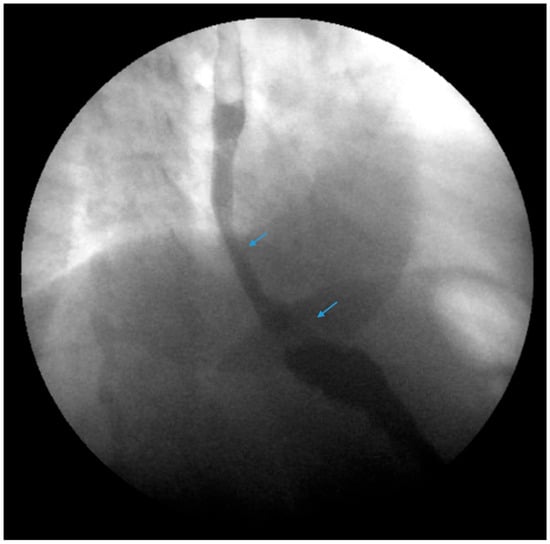

Figure 2.

An upper gastrointestinal series reveals a moderate, sliding type-one hiatal hernia (bottom arrow) in addition to gastroesophageal reflux disease (top arrow) in a patient with morbid obesity.